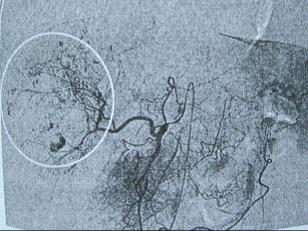

以下是肝动脉造影示肝血管瘤栓塞前后对比图

肝动脉造影示肝血管瘤呈“枯枝挂果征”(白圈)